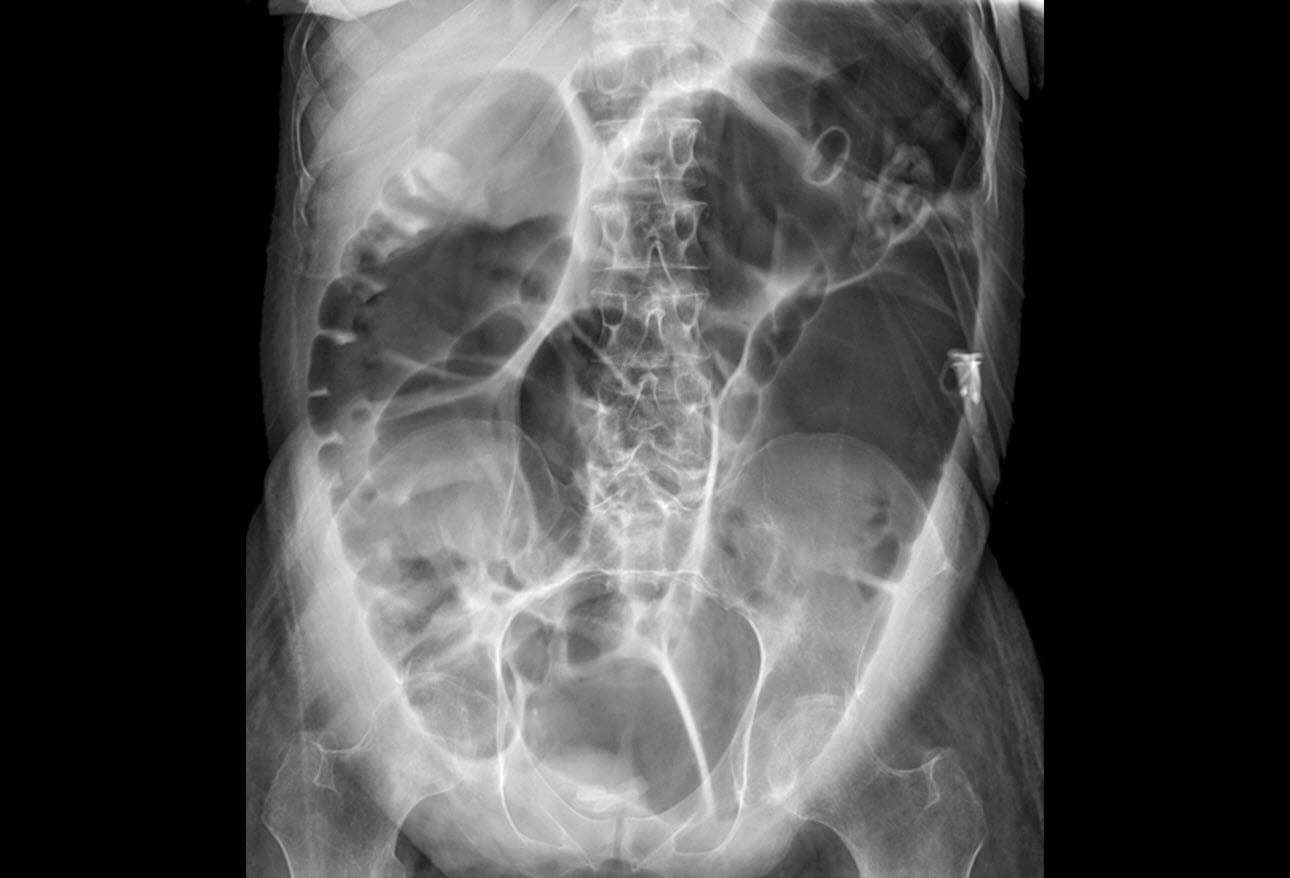

From medicolearning.com

Ogilvie’s Syndrome (AcuteColonic Pseudo Obstruction) MedicoLearning Ogilvie Syndrome Symptoms ogilvie syndrome is a rare disorder of colonic dilation and dysfunction that mimics mechanical obstruction. what are the symptoms of megacolon? Common symptoms of megacolon include constipation, bloating, and abdominal pain. Usually the patient has abdominal distention, pain and altered bowel movements. In some cases the small bowel. learn about the definition, causes, symptoms, diagnosis, treatment, and. Ogilvie Syndrome Symptoms.